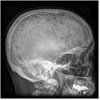

What is Paget’s Disease “Osteitis Deformans” and what is it caused by?

-Common chronic metabolic disease of the skeleton which causes excessive bone breakdown and disorganized new bone formation -Idiopathic diseases

280

What parts of the body does Paget’s Disease “Osteitis Deformans” affect?

Affects pelvis, femurs, skull, tibias, vertebrae, clavicles, and ribs

What are the radiographic signs of Paget's disease

Bones affected have a mottled, cotton-wool appearance (from irregular formation)